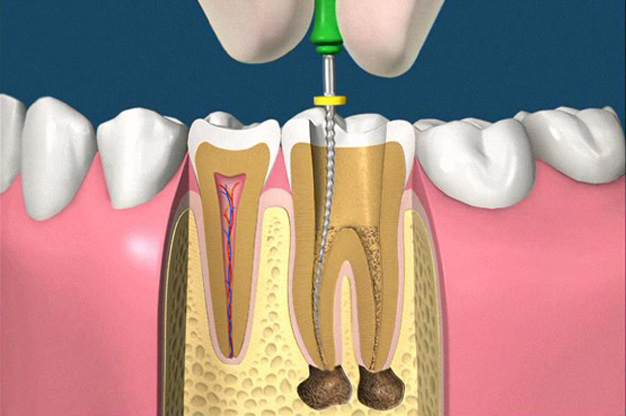

• accesso alla camera pulpare mediante frese diamantate

• asportazione della polpa e sagomatura dello spazio endodontico con strumenti meccanici (in nichel-titanio), con l'ausilio della detersione del canale radicolare (acqua ossigenata, ipoclorito di Sodio, calcio-chelanti)

• otturazione di tutto l'endodonto mediante materiali termoplastici (guttaperca) e cementi biocompatibili